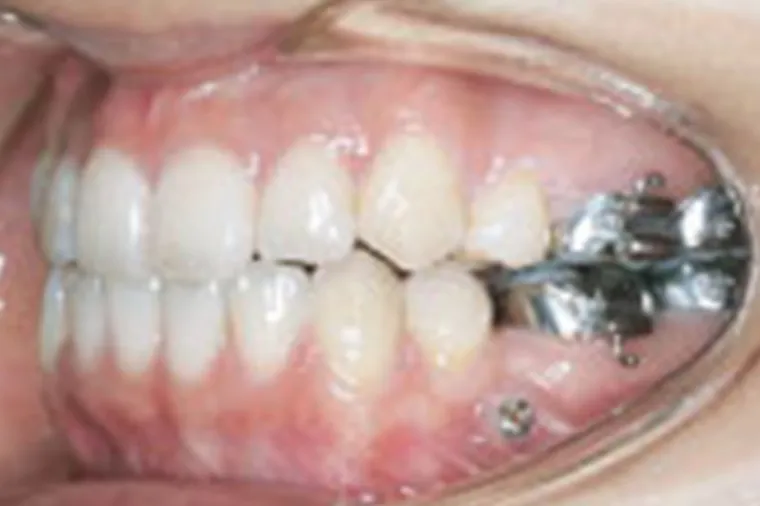

顎の骨に矯正治療用のアンカースクリュー(ねじ)を歯肉の下の骨に埋め込み、歯を動かすための固定源(支点)として利用する矯正治療法です。

通常のワイヤー矯正では、歯に装置を付けて互いに引っ張り合う構造のため、片側だけを動かしたい場合でも反対側の歯が一緒に動いてしまい、細かいコントロールが難しいという課題がありました。

アンカースクリューは埋め込んだ骨にしっかり固定されるため固定源が動かず、狙った方向に正確に歯を移動させることが可能です。従来では難しかった歯の移動や治療期間の短縮にもつながり、対応できる症例の幅が大きく広がりました。

歯科矯正用アンカースクリュー